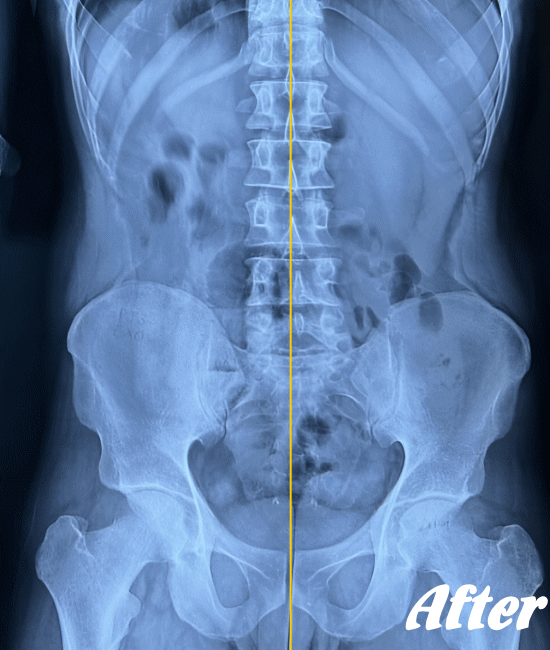

医療機関でも用いられているAKA療法を取り入れた施術により、身体に無理をかけず、ゆっくりと骨や関節の位置を解剖学的に正しい位置へ調整することで、痛みを取り除いていきます。慢性化した痛みも改善します。

多くの場合、骨盤の仙腸関節、腰の骨(腰椎)、そして足の付け根の股関節を調整すれば、痛みはなくなり、健康な状態に回復します。

ぎっくり腰程度であれば、初回の施術で腰が伸ばせる程度までには回復し、2回目の施術で残った痛みを取り除き、3回目で最後の違和感を解消します。